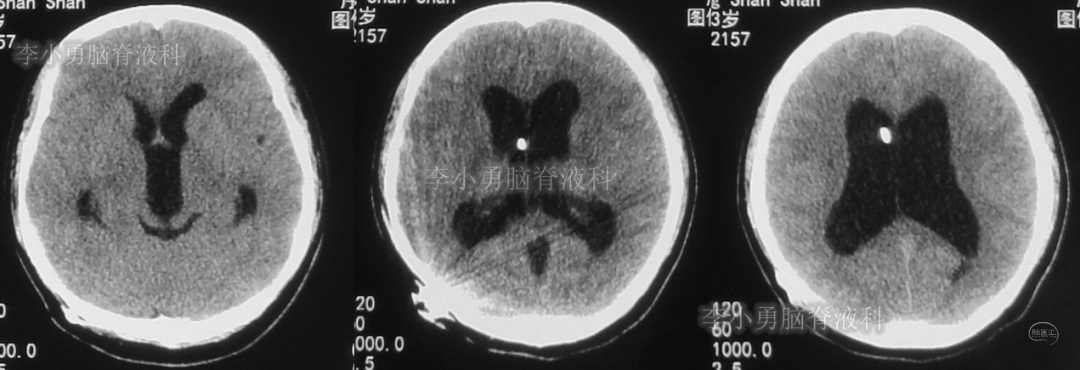

此后1个多月(2019年11月4日到2019年12月16日),患者意识一直无改善,一直呈模糊状态,多次复查头颅CT(图-12至图-20)见脑室大小反复变化不定,医生根据CT结果等反复多次调节分流泵压力(具体过程家属回忆不起)。但患者病情无好转却逐渐加重,逐渐不能咀嚼、吞咽及进食,卧床不起。

图-12:2019年11月8日头颅CT

图-13:2019年11月16日头颅CT

图-14:2019年11月19日头颅CT

图-15:2019年12月3日头颅CT

图-16:2019年12月10日头颅CT

图-17:2019年12月12日头颅CT

图-18:2019年12月13日头颅CT

图-19:2019年12月14日头颅CT

图-20:2019年12月16日头颅CT